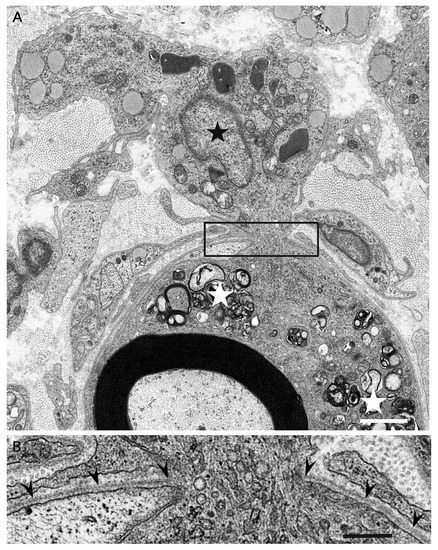

Macrophages and Autoantibodies in Demyelinating Diseases

Myelin phagocytosis by macrophages has been an essential feature of demyelinating diseases in the central and peripheral nervous systems, including Guillain–Barré syndrome (GBS), chronic inflammatory demyelinating polyneuropathy (CIDP), and multiple sclerosis (MS). The discovery of autoantibodies, including anti-ganglioside GM1 antibodies in the axonal [...] Read more.

Myelin phagocytosis by macrophages has been an essential feature of demyelinating diseases in the central and peripheral nervous systems, including Guillain–Barré syndrome (GBS), chronic inflammatory demyelinating polyneuropathy (CIDP), and multiple sclerosis (MS). The discovery of autoantibodies, including anti-ganglioside GM1 antibodies in the axonal form of GBS, anti-neurofascin 155 and anti-contactin 1 antibodies in typical and distal forms of CIDP, and anti-aquaporin 4 antibodies in neuromyelitis optica, contributed to the understanding of the disease process in a subpopulation of patients conventionally diagnosed with demyelinating diseases. However, patients with these antibodies are now considered to have independent disease entities, including acute motor axonal neuropathy, nodopathy or paranodopathy, and neuromyelitis optica spectrum disorder, because primary lesions in these diseases are distinct from those in conventional demyelinating diseases. Therefore, the mechanisms underlying demyelination caused by macrophages remain unclear. Electron microscopy studies revealed that macrophages destroy myelin as if they are the principal players in the demyelination process. Recent studies suggest that macrophages seem to select specific sites of myelinated fibers, including the nodes of Ranvier, paranodes, and internodes, for the initiation of demyelination in individual cases, indicating that specific components localized to these sites play an important role in the behavior of macrophages that initiate myelin phagocytosis. Along with the search for autoantibodies, the ultrastructural characterization of myelin phagocytosis by macrophages is a crucial step in understanding the pathophysiology of demyelinating diseases and for the future development of targeted therapies. Full article